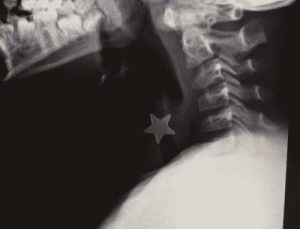

Stella di metallo in trachea, bimbo salvato al Niguarda